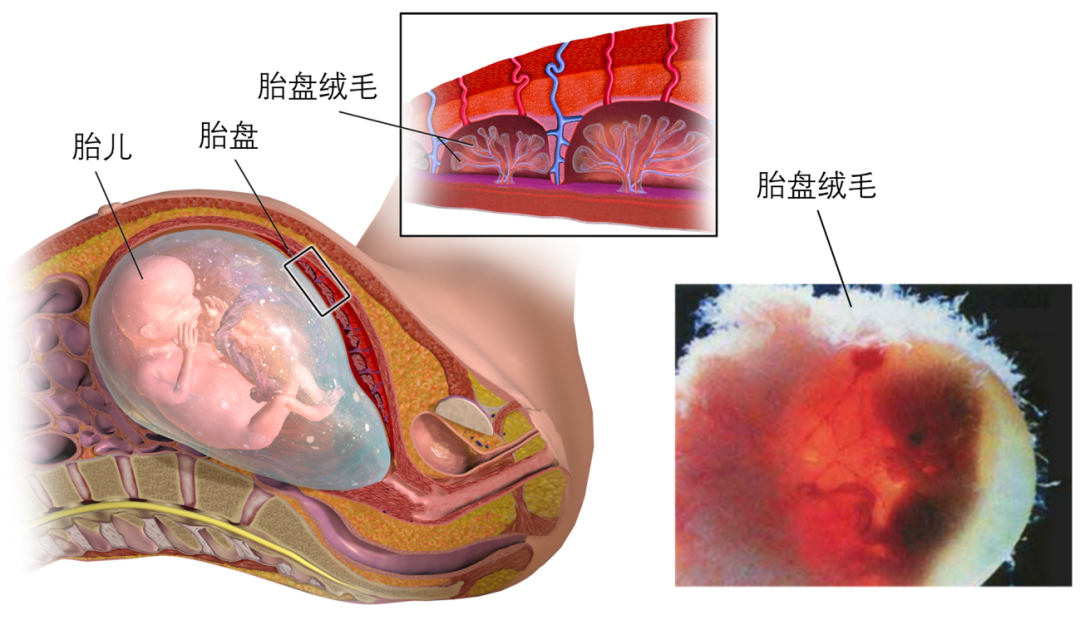

以螺蛳粉为例,当孕妈吃下螺蛳粉时,螺蛳粉中独特的气味分子首先会随着消化道的吸收,进入妈妈的血液。接着「带有螺蛳粉味的血液」在胎盘绒毛的作用下,迅速流向胎盘。

胎盘上有一种特殊的绒毛结构,这种结构有非常强的侵入性,能促进妈妈的血液更快地提供给胎盘。

图片来源:参考文献 [17]

当「带有螺蛳粉味的血液」充满胎盘的绒毛间隙时,螺蛳粉味的气味小分子物质很容易穿过羊膜,进入到羊水中。

胎盘的结构,气味小分子物质很容易穿过,并进入到羊水中。